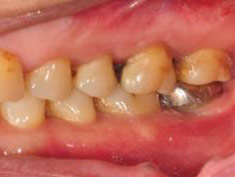

牙周初診時患者之口內觀。口內明顯牙菌斑及牙結石堆積。全口嚴重牙齦紅腫。治療前X光片。#37的近心側有較深的骨內缺損,剩餘齒槽骨高度只有20%。

第一階段牙周基本治療後,牙齦發炎狀況明顯獲得改善。